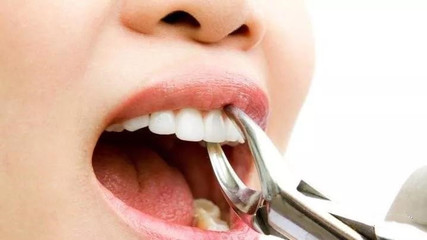

牙痛发生在与牙齿相关的部位发炎的时候。此时需要先进行抗炎治疗,防止炎症引起的其他疾病,等其他炎症消失后再进行牙齿治疗。2.医生不主张拔牙是基于局部解剖,患者一般情况,手术难度。牙痛求医的病例多见于急性牙周炎、牙槽脓肿、急性牙髓炎等。这些疾病需要经过止痛、药物治疗或引流、消炎后才能去除,视具体情况而定。

此外,牙齿急性炎症拔牙可能会导致炎症扩散,如智齿冠周炎,可能会引起牙周间隙蜂窝组织炎。遇到难拔的牙,手术时间长,损伤大,更容易引起并发症,甚至严重危及患者生命。对于年老体弱、患有急慢性疾病、抵抗力差的患者,急性炎症期间拔牙会加重病情,最好等到全身情况好转。

普通人认为牙疼就拔不了牙。其实有些情况下,牙疼就需要拔牙,需要拔牙。比如牙齿周围有脓肿,面部间隙有明显的感染和肿胀,全身有明显的菌血症,就必须拔牙。拔牙后才能顺利排脓,消炎止痛,才能缓解全身症状。当然,如果急性牙髓炎的牙齿没有保留价值,那么牙痛时也可以拔牙。

牙疼可以拔牙吗?你好!建议你先去医院检查一下。如果有牙髓炎,可以拔牙,因为还没有扩散到根尖,只是局部神经感染。如果根尖和根尖周组织有炎症,不能拔牙,就会感染。首先要控制炎症。牙齿疼的时候不能拔。只有在不疼消炎的情况下才能考虑拔牙,如果不是智齿就需要补牙。牙痛的时候不要拔牙。牙疼的原因有很多,可能是断牙暴露牙神经引起的疼痛,也可能是牙齿歪了或者智齿没长出来。

2.牙疼能不能拔牙的问题,要看是什么引起的疼痛。牙髓炎也会引起牙齿剧烈疼痛,但可以拔除。但如果是牙槽脓肿,一般需要等到炎症消除。3.牙疼要尽快找口腔科的牙医治疗。吃药效果不好,治标不治本,耽误病情。一般来说应该是牙周病。如果这颗牙是病变,确实需要拔除,就不能再保守治疗,应该果断拔除。

Hello: 1。牙疼的时候原则上是不允许拔牙的!主要是怕炎症扩散到间隙,但也有例外,比如牙痛,如果确定是牙髓炎早期,不涉及牙根,就可以摘除。2.以上拔牙只针对智齿,原则上除智齿外的牙齿都要尽量保留,疼痛可以通过“根管治疗”来解决。建议最好先找医生帮忙,再进行治疗。